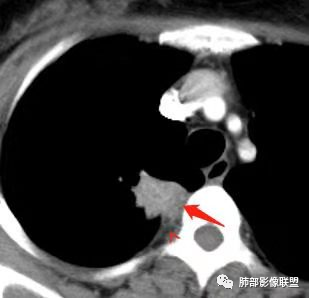

胸部CT:右肺上叶尖段脊柱旁实性结节灶,宽基底与胸膜接触,可见平直征、软毛刺、棘突、空泡,中心片状坏死,周围磨玻璃影边界不清,胸膜增厚、糊墙。增强呈环形强化。右肺下叶实性小结节,见长毛刺、胸膜牵拉。综合考虑:炎性病变,结核可能大。鉴别隐球菌、腺癌。

胸CT:右肺上叶尖段膜下实变病变,病灶边缘毛刺、棘突征、U型征、平直,病灶边缘可见毛玻璃影,纵隔窗可见病灶与胸膜间可见低密度,增强可见病灶强化,病灶内可见低密度区,静脉期较动脉期貌似强化明显,考虑肉芽肿性病变,结核?但病灶周围部分存在膨隆,恶性不除外。

右肺上叶胸膜下结节,边缘有平直、刀切征及桃尖征,病灶与胸膜呈宽基底,胸膜糊墙,这些征象均指向良性病灶;病灶内可见液化坏死区,壁相对厚,强化较显著;病灶周围较大范围磨玻璃影,边缘模糊,淡薄柔和,未见卫星结节或树丫,提示为一个急性渗出,这是符合炎性病灶脓肿形成的。

换个角度看,右肺上叶这肿瘤符合吗?如此小范围肿瘤灶很少能够在影像上观察到如此明显的坏死,内壁还如此光整?即便是鳞癌,更遑论腺癌及小细胞癌等,不要忘了这是中青年女性患者。

结核易形成空洞,但周围渗出如此明显,没有卫星灶,内壁如此圆整,厚壁强化如此明显,都很难与常见的结核灶关联起来。

会是什么感染?临床症状相对和缓,脓肿单发的,经验上尤以G-杆菌感染较为多见,如肺炎克雷伯杆菌等。